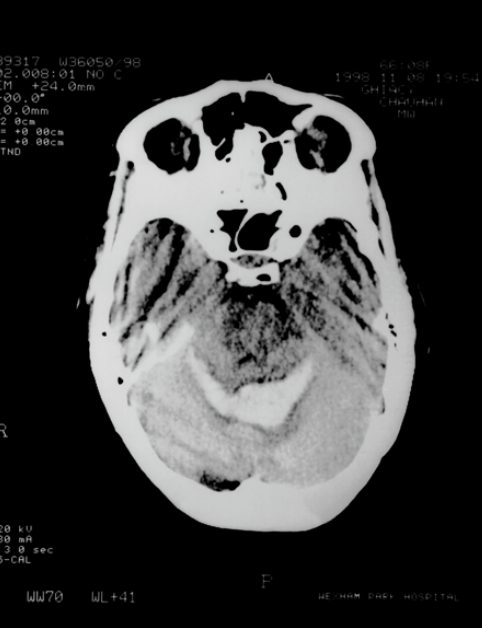

Examine the CT scans provided, identify any abnormalities that are present and suggest a diagnosis

Haemorrhagic stroke - affecting middle cerebral artery (fresh blood shows as white lesions on the CT scan)

Strokes - blockade VS haemorrhage, both present differently